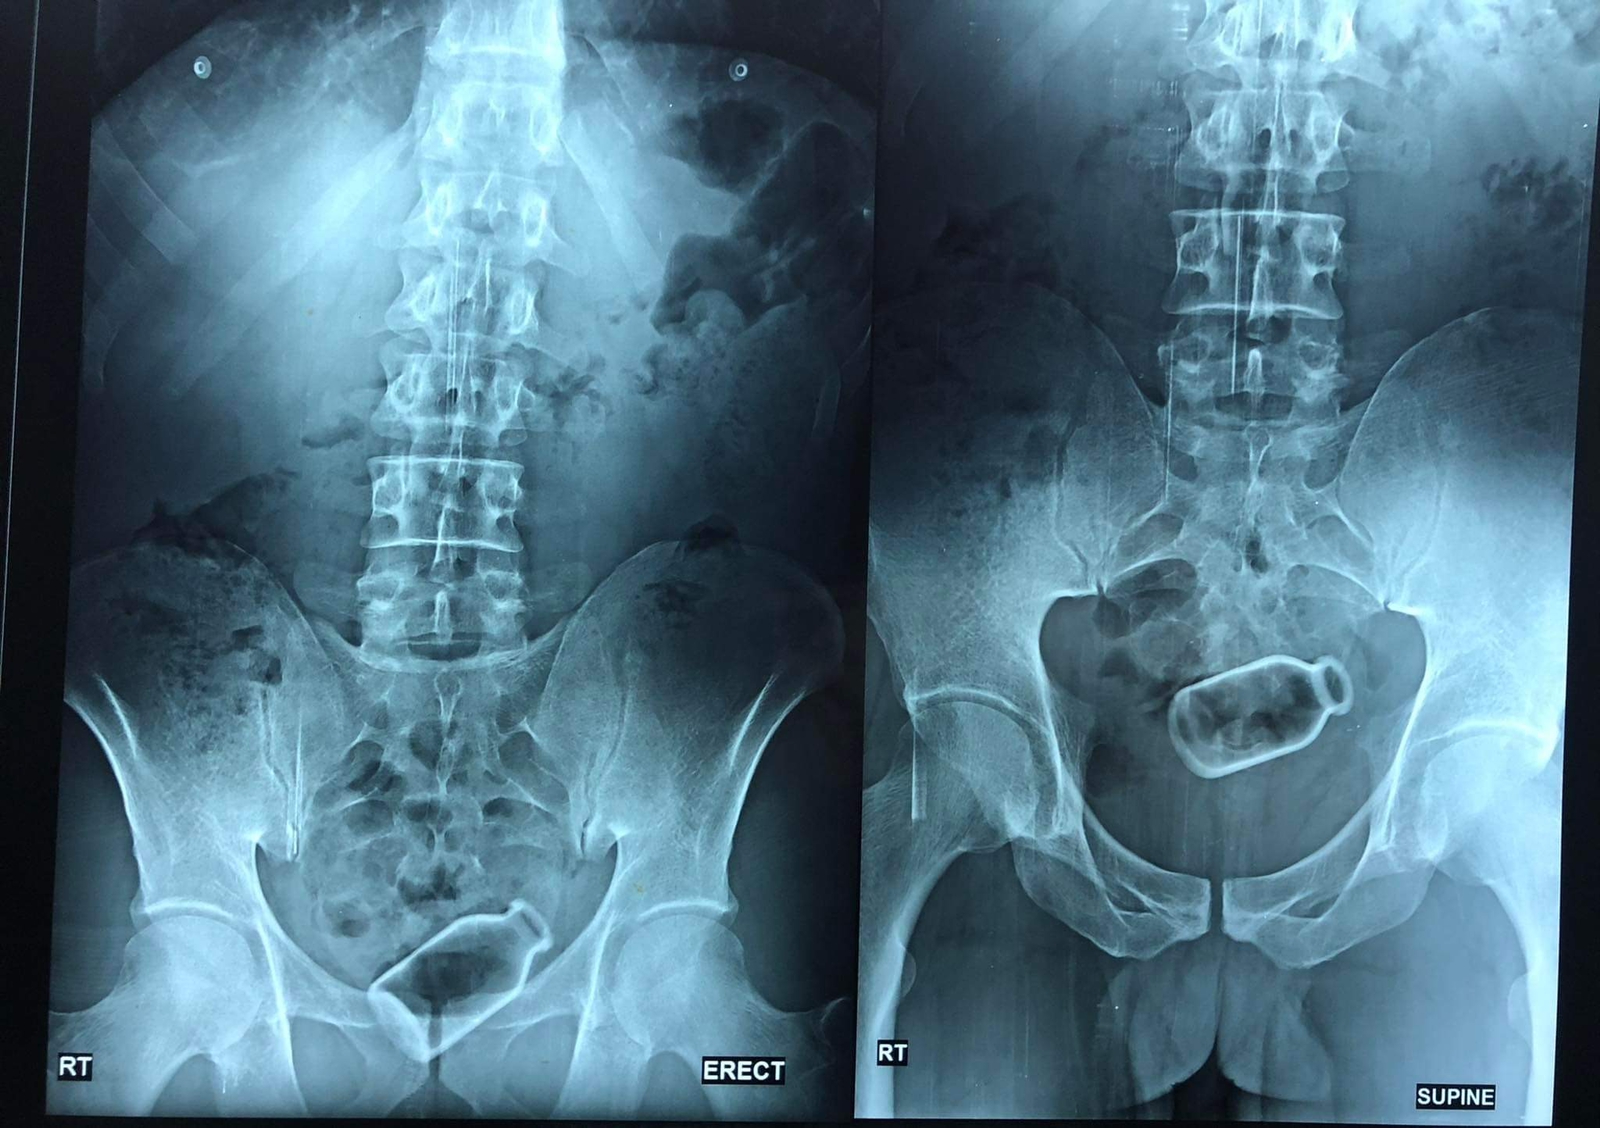

وتابعت دكتورة أسماء: المريض من المنوفية ويبلغ من العمر 38 عامًا، ويعاني من بعض الاضطرابات النفسية، وقمنا بإجراء العملية بأحد المستشفيات الخاصة بالمنصورة، وأجرينا بعض الآشعة للمريض، ووجدنا أن الزجاجة مستقرة في مكانها ولم تقم بعمل ثقب في القولون، وكانت على بعد 20 سم من فتحة الشرج، وهذه مسافة بعيدة نسيبيًا، ومن الطبيعي عند وجود جسم غريب في القولون يكون قريبا من فتحة الشرج، وعادة يتم استخراجه عن طريق الجراحة أو اليد، ولكن تلك الزجاجة بسبب بعدها كان استخراجها عن طريق اليد صعبا، لذلك قررنا استخدام الأجهزة ودون إجراء جراحة في تلك العملية، وكانت العملية صعبة، حيث إن الجسم كان زجاجيا وكنا نخشى من انكسار الزجاجة بداخله واللجوء للجراحة، والأجهزة في العادة تتعامل مع الأنسجة.

وأوضحت الدكتورة، أنه عن طريق الآلات والأجهزة الطبية، ودون جراحة، تمكنا من استخراج الزجاجة من قولون المريض في عملية استغرقت حوالي ساعة.